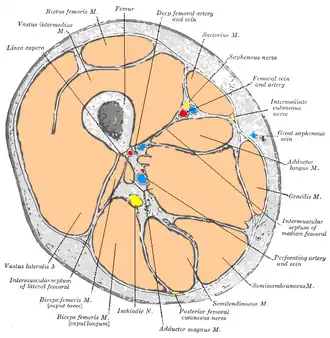

- The vastus intermedius muscle lies between vastus lateralis and vastus medialis on the front of the femur (i.e., on the top or front of the thigh), but deep to the rectus femoris muscle. Typically, it cannot be seen without dissection of the rectus femoris.[1]

Cross-section through the middle of the thigh

Cross-section through the middle of the thigh -